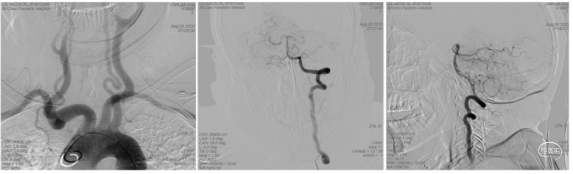

既往史:高血压病史10余年,平素不规律服药,血压控制欠佳。入院急诊心电图示:窦性心律。入院时NIHSS 19分,予以阿替普酶(50mg)静脉溶栓,直接桥接治疗。

术前CT:转入我院后急行CT检查,未见明显出血,左侧大脑后动脉条索状高密度影(图1),因患者自发病在6小时内。

手术过程:局麻,右美托咪定镇静,5F造影导管行造影检查,结果提示:左侧椎动脉相对优势,V1段连续复合弯;左侧大脑后动脉P1段中段开始远端未见显影(下图2)。

将6F 088 Neuron MAX长鞘输送至左侧椎动脉V2段中段, Powler微导管、Transend微导丝(300cm)行“首过效应”判断可见:原闭塞部位缓慢前向血流后撤出微导管,同轴交换跟进4 MAX抽吸导管(下图1)。

一次性抽吸取栓成功开通左侧大脑后动脉,造影显示左侧大脑后动脉全程显影良好,流速正常,P2段局部稍狭窄,无明显造影剂外溢(图2、3 )。

结束手术,体外见一黄白色长条状栓子(图4),股动脉穿刺至大脑后动脉再通。

术后患者镇静状态,NIHSS评分未评。

术后镇静、镇痛、控制血压,术后动态复查头颅CT见左侧枕叶、丘脑、中脑片状梗死区,无明显出血。术后予以拜阿司匹林(100mg)、硫酸氢氯吡格雷(75mg)、阿托伐他汀(60mg)。患者于术后第1天清醒,神经功能逐渐改善。

急诊核磁DWI示左侧小脑及延髓新发梗死。

MRA示左侧椎动脉颅内段闭塞,闭塞段呈杯口征。

结合患者CT及核磁影像,考虑患者左侧椎动脉颅内段系急性闭塞,闭塞端呈杯口征,栓塞可能性大。向患者家属详细交代病情,考虑栓塞可能性大,因患者基底动脉走形较直,考虑血栓可能骑跨位于左侧小脑后下动脉及椎基底汇合部,有继续向远端脱落导致基底动脉闭塞风险。

分析造影考虑患者原先血栓符合术前判断,骑跨位于小脑后下动脉及椎基底动脉汇合部,在搬动过程中,椎基底汇合部血栓再次崩解移位,最终左椎颅内段通畅,但左侧小脑后下动脉闭塞,右侧大脑后动脉远端血栓异位。

考虑患者年轻,左侧椎动脉优势,左侧小脑后下动脉供血范围较大,若不能及时开通血管,可能导致小脑大面积梗死,后继出现脑水肿,脑疝几率较大,向患者家属交代手术风险后家属积极要求介入治疗。

快速建立8F导引导管+CAT6中间导管建立路径,微导丝携微导管顺利通过左侧小脑后下动脉闭塞段。4/20取栓支架输送到位下图2;释放取栓支架下图3;取栓支架释放后造影血管未再通下图4。

等待5分钟后,部分回收微导管,钳夹血栓,上送中间导管,采用SWIM技术取栓,一次钳夹取出的暗红色血栓。复查造影见左侧小脑后下动脉完全再通。

术前术后对比

动态观察15分钟后,左侧小脑后下动脉血流通畅,右侧大脑后动脉远端血栓逐渐消融,持续静脉泵入替罗非班,逐级撤出各级导管,结束手术。